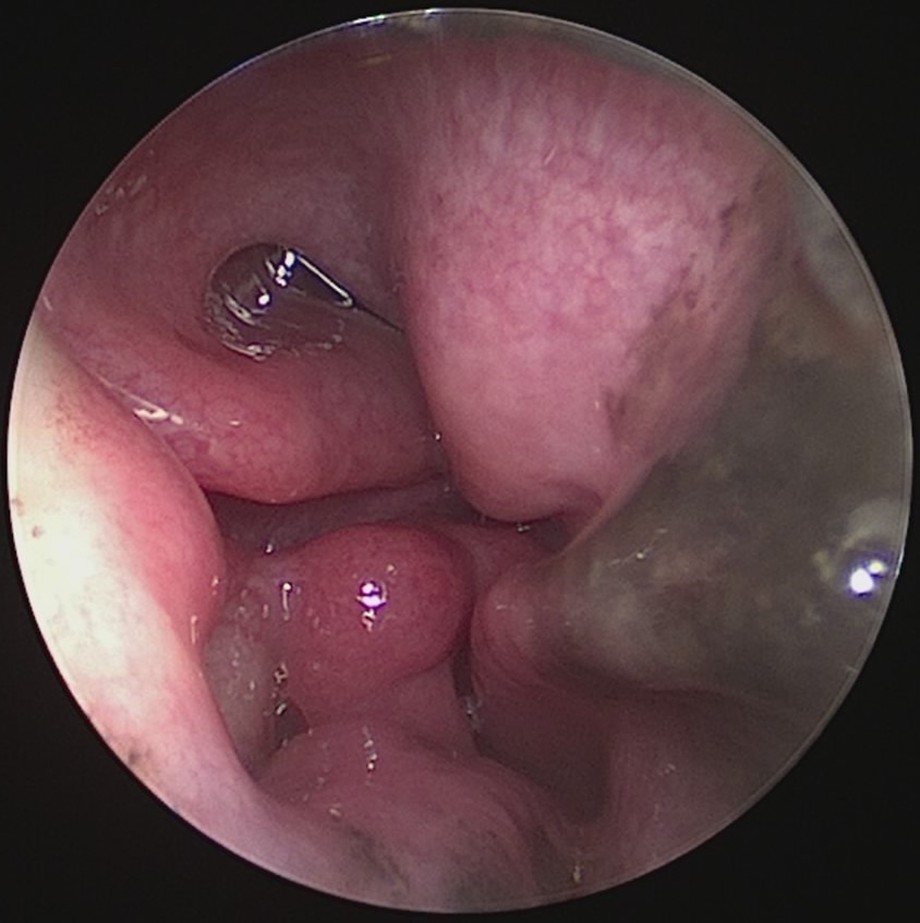

- Zunge vor dem Eingriff

Die Volumenreduktion des Zungengrundes wird bei Patienten eingesetzt, die eine Vergrößerung oder Erschlaffung der Zungenmuskulatur aufweisen. Der Zungengrund wird durch den Eingriff stabilisiert und die Atemwege erweitert. Die Gewebe- und Organoberflächen bleiben intakt, was kaum zu postoperativen Schmerzen führt, und das Infektionsrisiko vermindert. Eine sichtbare Volumenreduktion und Straffung des Gewebes ist innerhalb von 6 Wochen zu sehen. Meist sind nur zwei Behandlungstermine notwendig.

Hierbei kommt die CELON Methode zum Einsatz- Es handelt es sich um eine bipolare radiofrequenzinduzierte Thermotherapie (RFITT) die eine minimalinvasive und impedanzkontrollierte Gewebeablation darstellt. Diese Methode ist sehr schonend, schnell und hoch effizient. Der Patient kann nach der Behandlung die Praxis sofort verlassen und hat somit keine Ausfallszeiten. Diese Methode schützt die Organoberflächen (Mukosa, Flimmerepithel) und verursacht keine Schmerzen während und nach dem Eingriff.